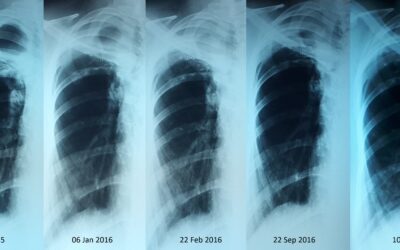

პაციენტი 49 წლის მამაკაცი. 2007 წ-ს ჩაუტარდა ტუბსაწინააღმდეგო ქიმიოთერაპია ფილტვების ტუბერკულოზის გამო. 2015 წ-ს ჰქონდა რელაფსი. წლების განმავლობაში პაციენტს ჰქონდა ქოშინი, მზარდი სუნთქვის უკმარისობა, რის გამოც ხშირად საჭიროებდა ჰოსპიტალიზაციას. 2016 წლის...